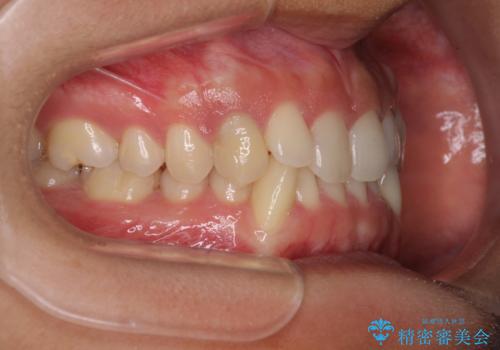

- 下顎の八重歯を気にして来院された患者様です。

マウスピース矯正でもワイヤー矯正でも対応可能であり、マウスピースによる治療を希望されたため、インビザラインを用いることとしました。

下顎前歯にデコボコが集中していたため、顎間ゴムによる後方移動とIPR(歯と歯の間を削ること)により歯列を整えることとしました。

しっかりとマウスピースを装着してくださったおかげで、スムーズに治療を終えることができました。

矯正治療途中で右下奥歯の虫歯治療を近医で行ったようで、既に神経が失活していたと合わせて矯正治療後に補綴治療を行う予定です。